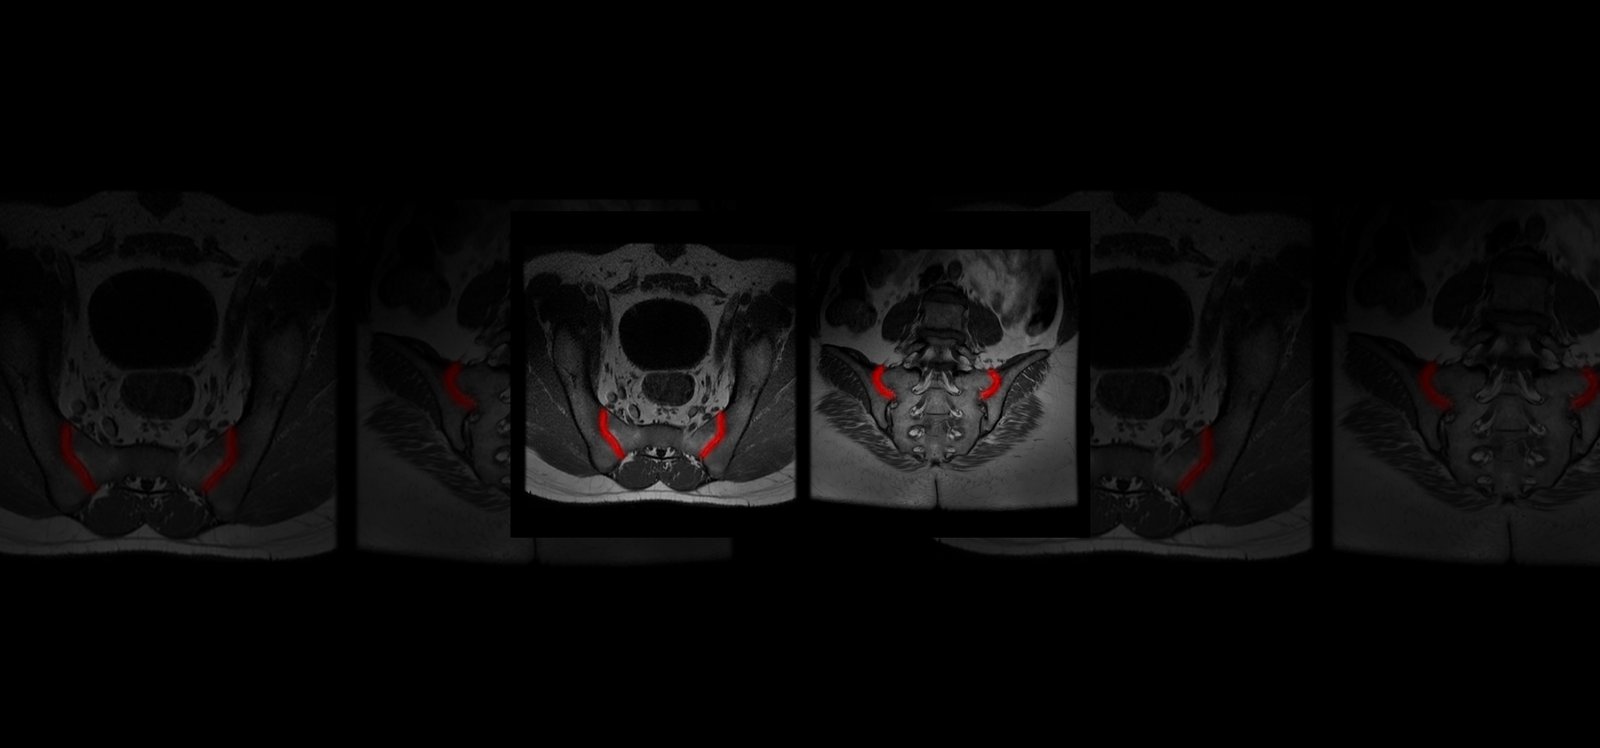

Quibim, in collaboration with a top-tier biopharmaceutical company, is conducting a retrospective observational real-word study with data from six sites world-wide (NCT06591481). The training dataset consists of 600 MRIs of the sacroiliac joint (SIJ) including a T1-weighted and STIR and/or T2 fat saturated sequence in coronal-oblique planes acquired at diagnosis and follow-up. For the validation process, an external sample of 200-300 MRIs with and without axSpA are being collected. QP-Insights® platform is being used for the image collection and processing. A double reading according to the Assessment of Spondylarthritis international Society (ASAS) criteria is being performed by radiologists with 12+ years of experience and a third reader for adjudication. The reading process consists of the classification into axSpA +/- and identification of the main findings: bone marrow edema (BME), ankylosis, erosion and fat metaplasia. An artificial intelligence (AI) based classification model will be developed to categorize patients as axSpA-positive (axSpA+) or axSpA-negative (axSpA-). Additionally, as an exploratory objective, the model will further stratify patients based on the main findings identified.